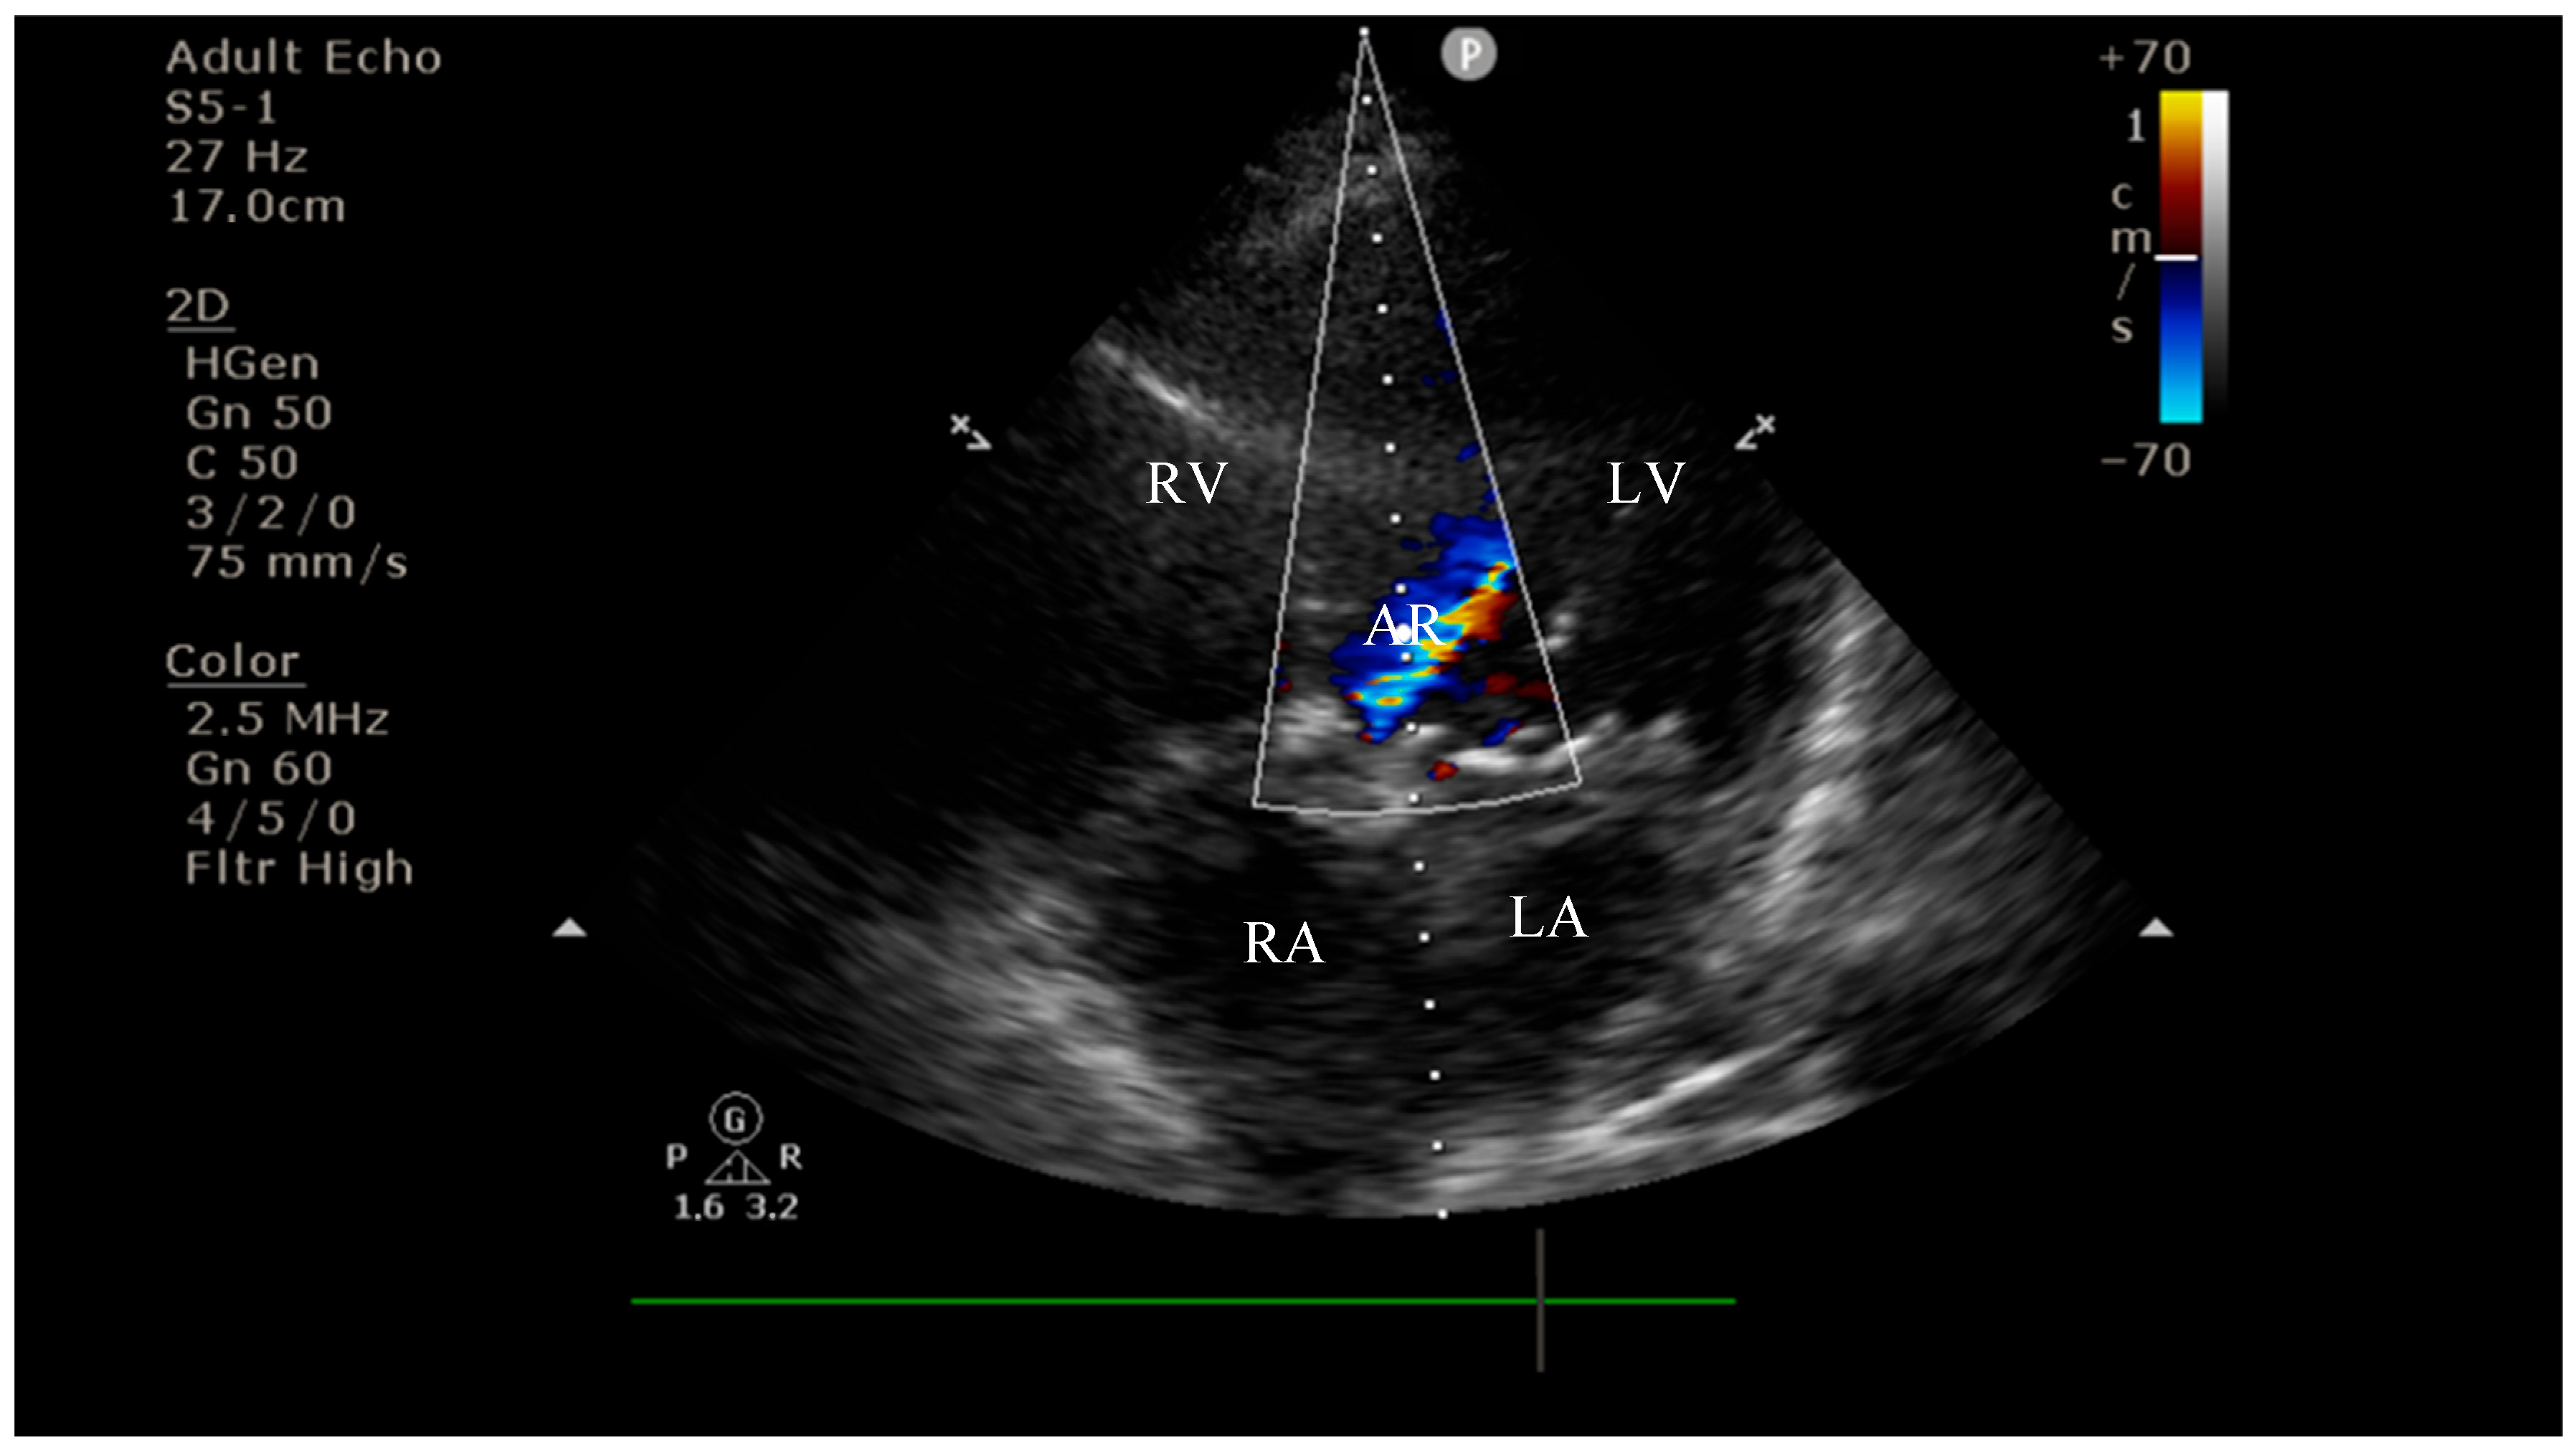

4.2. Diagnostic Findings: Mitral Valve Dysfunction and Embolic Phenomena

4.3. Coronary Complications and Diagnostic Dilemma